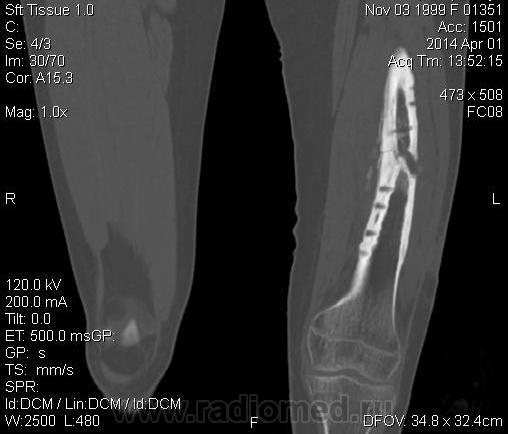

Молодая дама (14 лет) с переломом срдней трети диафиза левого бедра в анамнезе (декабрь 2012 г). Ломала ногу несколько раз в этом месте. Сейчас состояние после МОС. Как следует понимать изменения в кости, формируется ли ложный сустав?

Похоже ложный сустав сформировался. Но при нём обычно большие напластования костной мозоли, здесь их нет. В таких случаях смотрю при скопии подвижность.

Ох, не хочется думать о ложном суставе в 14 лет... По срокам под ложный сустав подходит, он характеризуется замыканием костномозгового канала с формированием подобий суставных поверхностей. У нее же есть хиленькая периостальная костная мозоль по задней поверхности бедра удерживающая отломки в правильном положении. Я склонна думать, что это скорее застарелый перелом (оно же замедленная консолидация). Здесь очень важно посмотреть предыдущие снимки (поиск рефрактуры, либо отсутствия полной консолидации).

Настоящего, родного ложного сустава пока нет, хотя костномозговой канал дистального отломка уже закрыт - образовалась склерозированная замыкательная пластина. Варусная деформация почти в 165 градусов... Я бы заключилась неполной консолидацией и варусной деформацией, прогностически формирование ложного сустава очень вероятно.